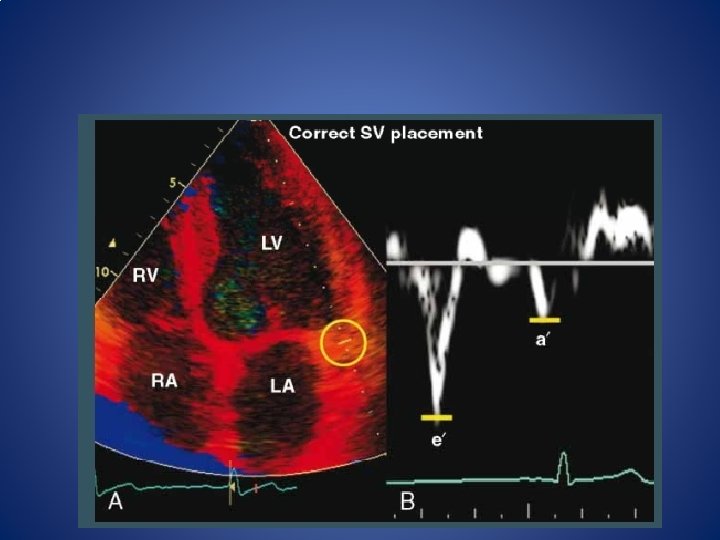

TDI - acquisition • PW apical view • The sample volume should be positioned at or 1 cm within the septal and lateral insertion sites of the mitral leaflets. • sweep speed of 50 to 100 mm/s at end-expiration ; average of >/= 3 consecutive cardiac cycles. • For the assessment of global LV diastolic function, it is recommended to acquire and measure tissue Doppler signals at least at the septal and lateral sides of the mitral annulus and their average. • In patients with cardiac disease, e’ can be used to correct for the effect of LV relaxation on mitral E velocity, and the E/e’ ratio can be applied for the prediction of LV filling pressures. • The E/e’ ratio is not accurate as an index of filling pressures in normal subjects or in patients with heavy annular calcification, mitral valve disease and constrictive pericarditis

TDI • Early diastolic filling velocity (e′) • Filling velocity after atrial contraction (A′) • Ratio of early to atrial diastolic myocardial velocity (e′/A′) • Ratio of transmitral blood flow velocity to tissue Doppler velocity (E/e′)

Medial vs lateral annular velocities • use the average (septal and lateral) e´ velocity in the presence of regional dysfunction • septal E/e´ ratio <8 is usually associated with normal LV filling pressures a ratio >15 is associated with increased filling pressures • between 8 and 15, other echocardiographic indices should be used. • In normal EFs, lateral tissue Doppler signals(E/e ánd e´/a´) have the best correlations with LV filling pressures and invasive indices of LV stiffness.